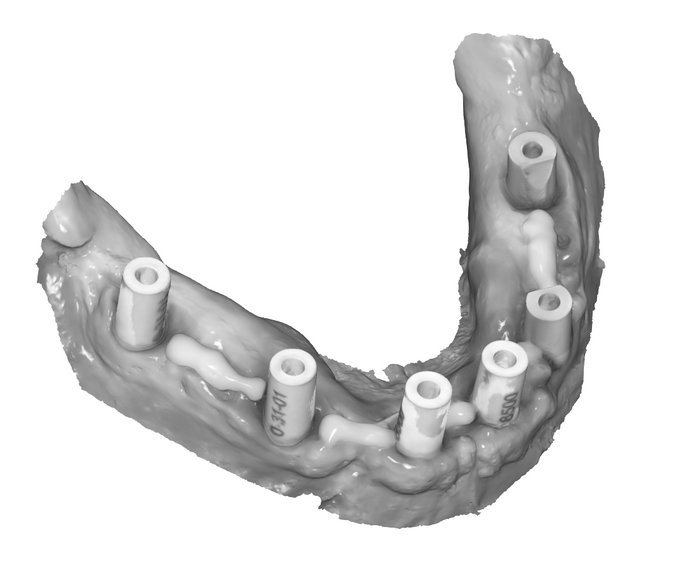

Мы распечатали шаблоны, которые помогал проектировать зубной техник Михаил:

Напомню, что шаблон не один, их много - базис, для сверления и досверливания (2 штуки), постановка и ложка. К базису крепятся составные части магнитами. Хотя, когда случаются особые случаи, всё крепится по-старинке, острыми и длинными "копьями" - пинами.

Я уже писала о распечатанном прототипе, точно повторяющем верхнюю челюсть пациента - вот, теперь показываю его вам.